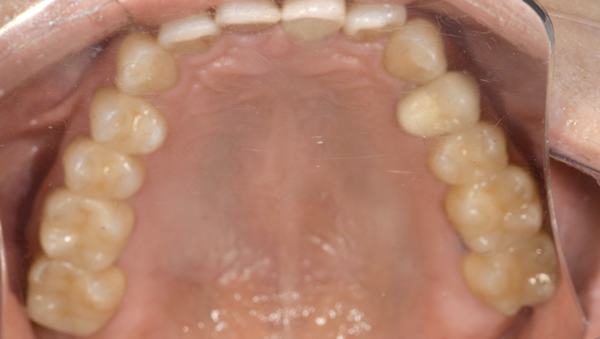

治療前:上の歯

担当医師所見:

臼歯部に残根状態の歯牙があり、またカリエス(虫歯)の散在が認められる。残根部分の両隣在歯は欠損部に対して傾斜し始めている。

治療前:下の歯

下顎右側臼歯部には一見大きな問題はないように見えるが、 頰側にフィステルと言われる排膿路があり発赤と主張があり炎症状態が続いていた。